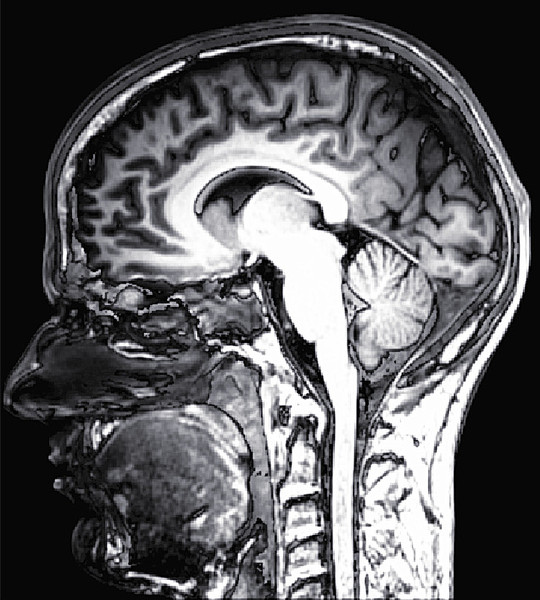

美國研究發現,思覺失調症、躁鬱症及情感型精神分裂等精神疾病患者,腦部與記憶功能有關的「海馬迴」部位都會發生皺縮而缺損的情形。(photo by deradrian on Flickr- used under Creative Commons license)

【台灣醒報記者李昀澔綜合報導】精神病患者的大腦「體積」恐因萎縮,而較健康者小。哈佛大學醫學院團隊發表於《美國醫學會期刊》的研究指出,包括思覺失調症(俗稱精神分裂)、躁鬱症,以及合併幻聽、幻視、被害妄想等思覺失調症狀,與躁鬱症狀的「情感型精神分裂」患者,腦部結構都有明顯的缺損。

研究人員比對5百餘名精神疾病患者與健康者的大腦體積,結果發現所有患者大腦「海馬迴」部位的組織都出現皺縮情形,且皺縮程度越高,患者妄想、記憶喪失、認知功能退化的狀況也越嚴重。

研究人員馬歇里卡夏凡接受「今日醫學新聞」網站訪問時解釋,海馬迴與記憶「存取」有關,精神疾病患者未必有記憶明顯喪失的情形,但多數都會發生無法分辨記憶形成的正確時間,也就是對各事件「時序」產生錯亂的狀況。他表示,未來研究重點包括釐清患者經治療後,海馬迴部位的皺縮狀況能否獲得改善。